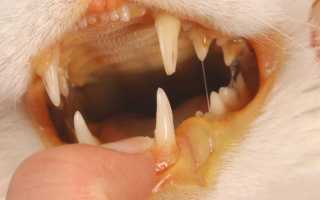

Гнойные выделения из носа и глаз являются характерным признаком микоплазмоза.

При поражении суставных элементов наблюдается нарушение двигательных функций животного, что отчетливо отслеживается по его походке – кошка хромает, поджимает лапки, долго не может находиться в стоячем положении.